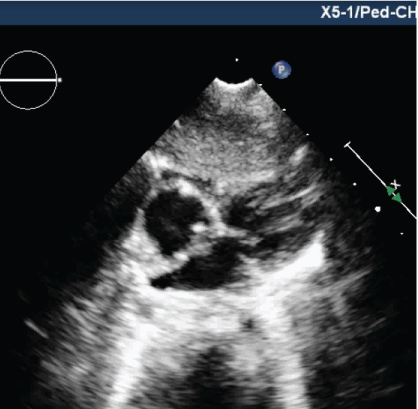

A two-months-old girl suffering weakness, anorexia, vomiting and growth retardation presented to our hospital. She was diagnosed Bartter syndrome. In her history, it was learned that she was hospitalized for sepsis, pneumonia and was cannulated with the umbilical venous catheter. Seventh day of the birth, echocardiography performed due to murmur had no additional pathology other than foramen ovale. In her physical examination, the heart rate was 136/bpm, respiratory rate was 28/min, blood pressure was 85/52 mmHg, and peripheral oxygen saturation was 94% by pulse oximetry. The patient had no dyspnea. There was a 2/6 systolic murmur over mesocardiac area. Complete blood count revealed leucocyte: 14.000/mm3, hemoglobin: 11 g/dl, platelet: 280000/mm3. Hepatic and renal function tests, C reactive protein were in normal ranges and blood cultures were negative. Chest X-ray and electrocardiography were also normal. Echocardiographic (ECHO) examination revealed that foramen ovale was patent with left to right shunting. An echodense fibromuscular membran like a thrombosis with dimensions 23*5 mm and which not obstruct the blood flow, was observed in the right atrium cavity between the right atrium anterior wall and the coaptation area of the tricuspid valve leaflets (Figure 1A and Figure 1B). There was no known familial history of thromboembolic disease and examination for thrombophilia was normal. Factor V Leiden, MTHFRC677T, MTHFR A1298C and the prothrombin 20210 gene mutations were not detected, the prothrombotic work-up, including assessment of antithrombin III, protein C: 0.84 (0.65-1.54), protein S, antiphospholipid antibodies, homocystein, was within normal limits. Human cytomegalovirus infection, another possible cause of neonatal thrombosis was also excluded. We observed that the thrombosis was completely resolved after sixteen day of subcutan enoxaparin treatment with therapeutic dose (2 mg/kg per day, 2 doses) (Figure 2). After complete resolution of thrombosis, it was continued for 3 months with a prophylactic dose (one dose per day).

Figure 1: Two dimensional echocardiographic view of the thrombosis (Original). View Figure 1